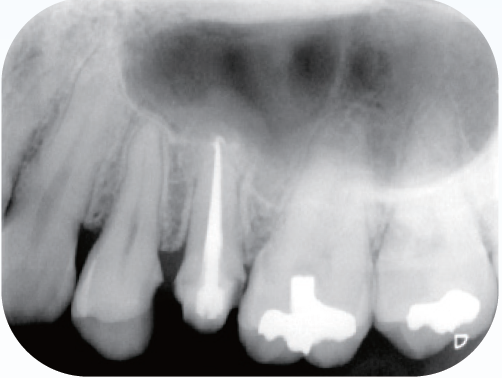

<術前>

覆髄材が近心髄角部付近まで充填されていて慢性の刺激により歯髄腔の狭窄が見られる。近心根根管口付近は遠心方向への規制があり、器具の根尖部への到達性を妨げている。

<術後>

近心根の根管口付近は湾曲度の修正形成が行われ、比較的緩やかな湾曲根管の処置になった。遠心根は根管口から根尖部まで連続したテーパーが付与され、根管充填時のプラガーの圧は適正に伝わり、根尖付近の複数の開口部に根管充填材が行き渡っていることが確認できる。